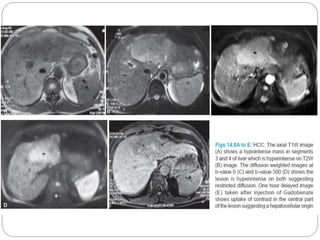

Hepatocellular carcinoma and regenerative nodule.

T1w MRI (A) and T2w MRI (B) demonstrating a hepatocellular

carcinoma (white arrowhead) and an adjacent atypical regenerative

nodule (black arrowhead).

Majority of hepatomas have decreased signal intensity on T1WI

-increased signal -fat or glycogen content

Hepatocellular carcinoma andregenerative nodule. T1w MRI (A) and T2w MRI (B) demonstrating a hepatocellular carcinoma (white arrowhead) and an adjacent atypical regenerative nodule (black arrowhead). Majority of hepatomas have decreased signal intensity on T1WI -increased signal -fat or glycogen content